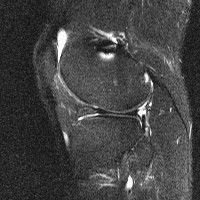

무릎 mri 간단히 봐주실 수 있으시나요 ㅠㅠ

안녕하세요 8년전 십자인대 수술하고 최근 무리한 운동에 무릎 불편감이 생겨서

mri 찍었습니다.

진단결과는 첫 찍은 병원에서 활액막염 이라는 진단을 받았습니다. 혹시 봐주실 수 있으실까요?

올라온 MRI가 단편적이라서 정확한 진단에 어려움이 있지만 십자인대에는 큰 이상이 있지는 않은것 같으며, 무릎관절내 물이 있는 것으로 보아 활액막염의 진단이 맞을 것 같습니다.

하지만 단편적인 영상이기 때문에 촬영병원에서 정확한 판독지 등을 받으시는 것이 좋겠습니다.